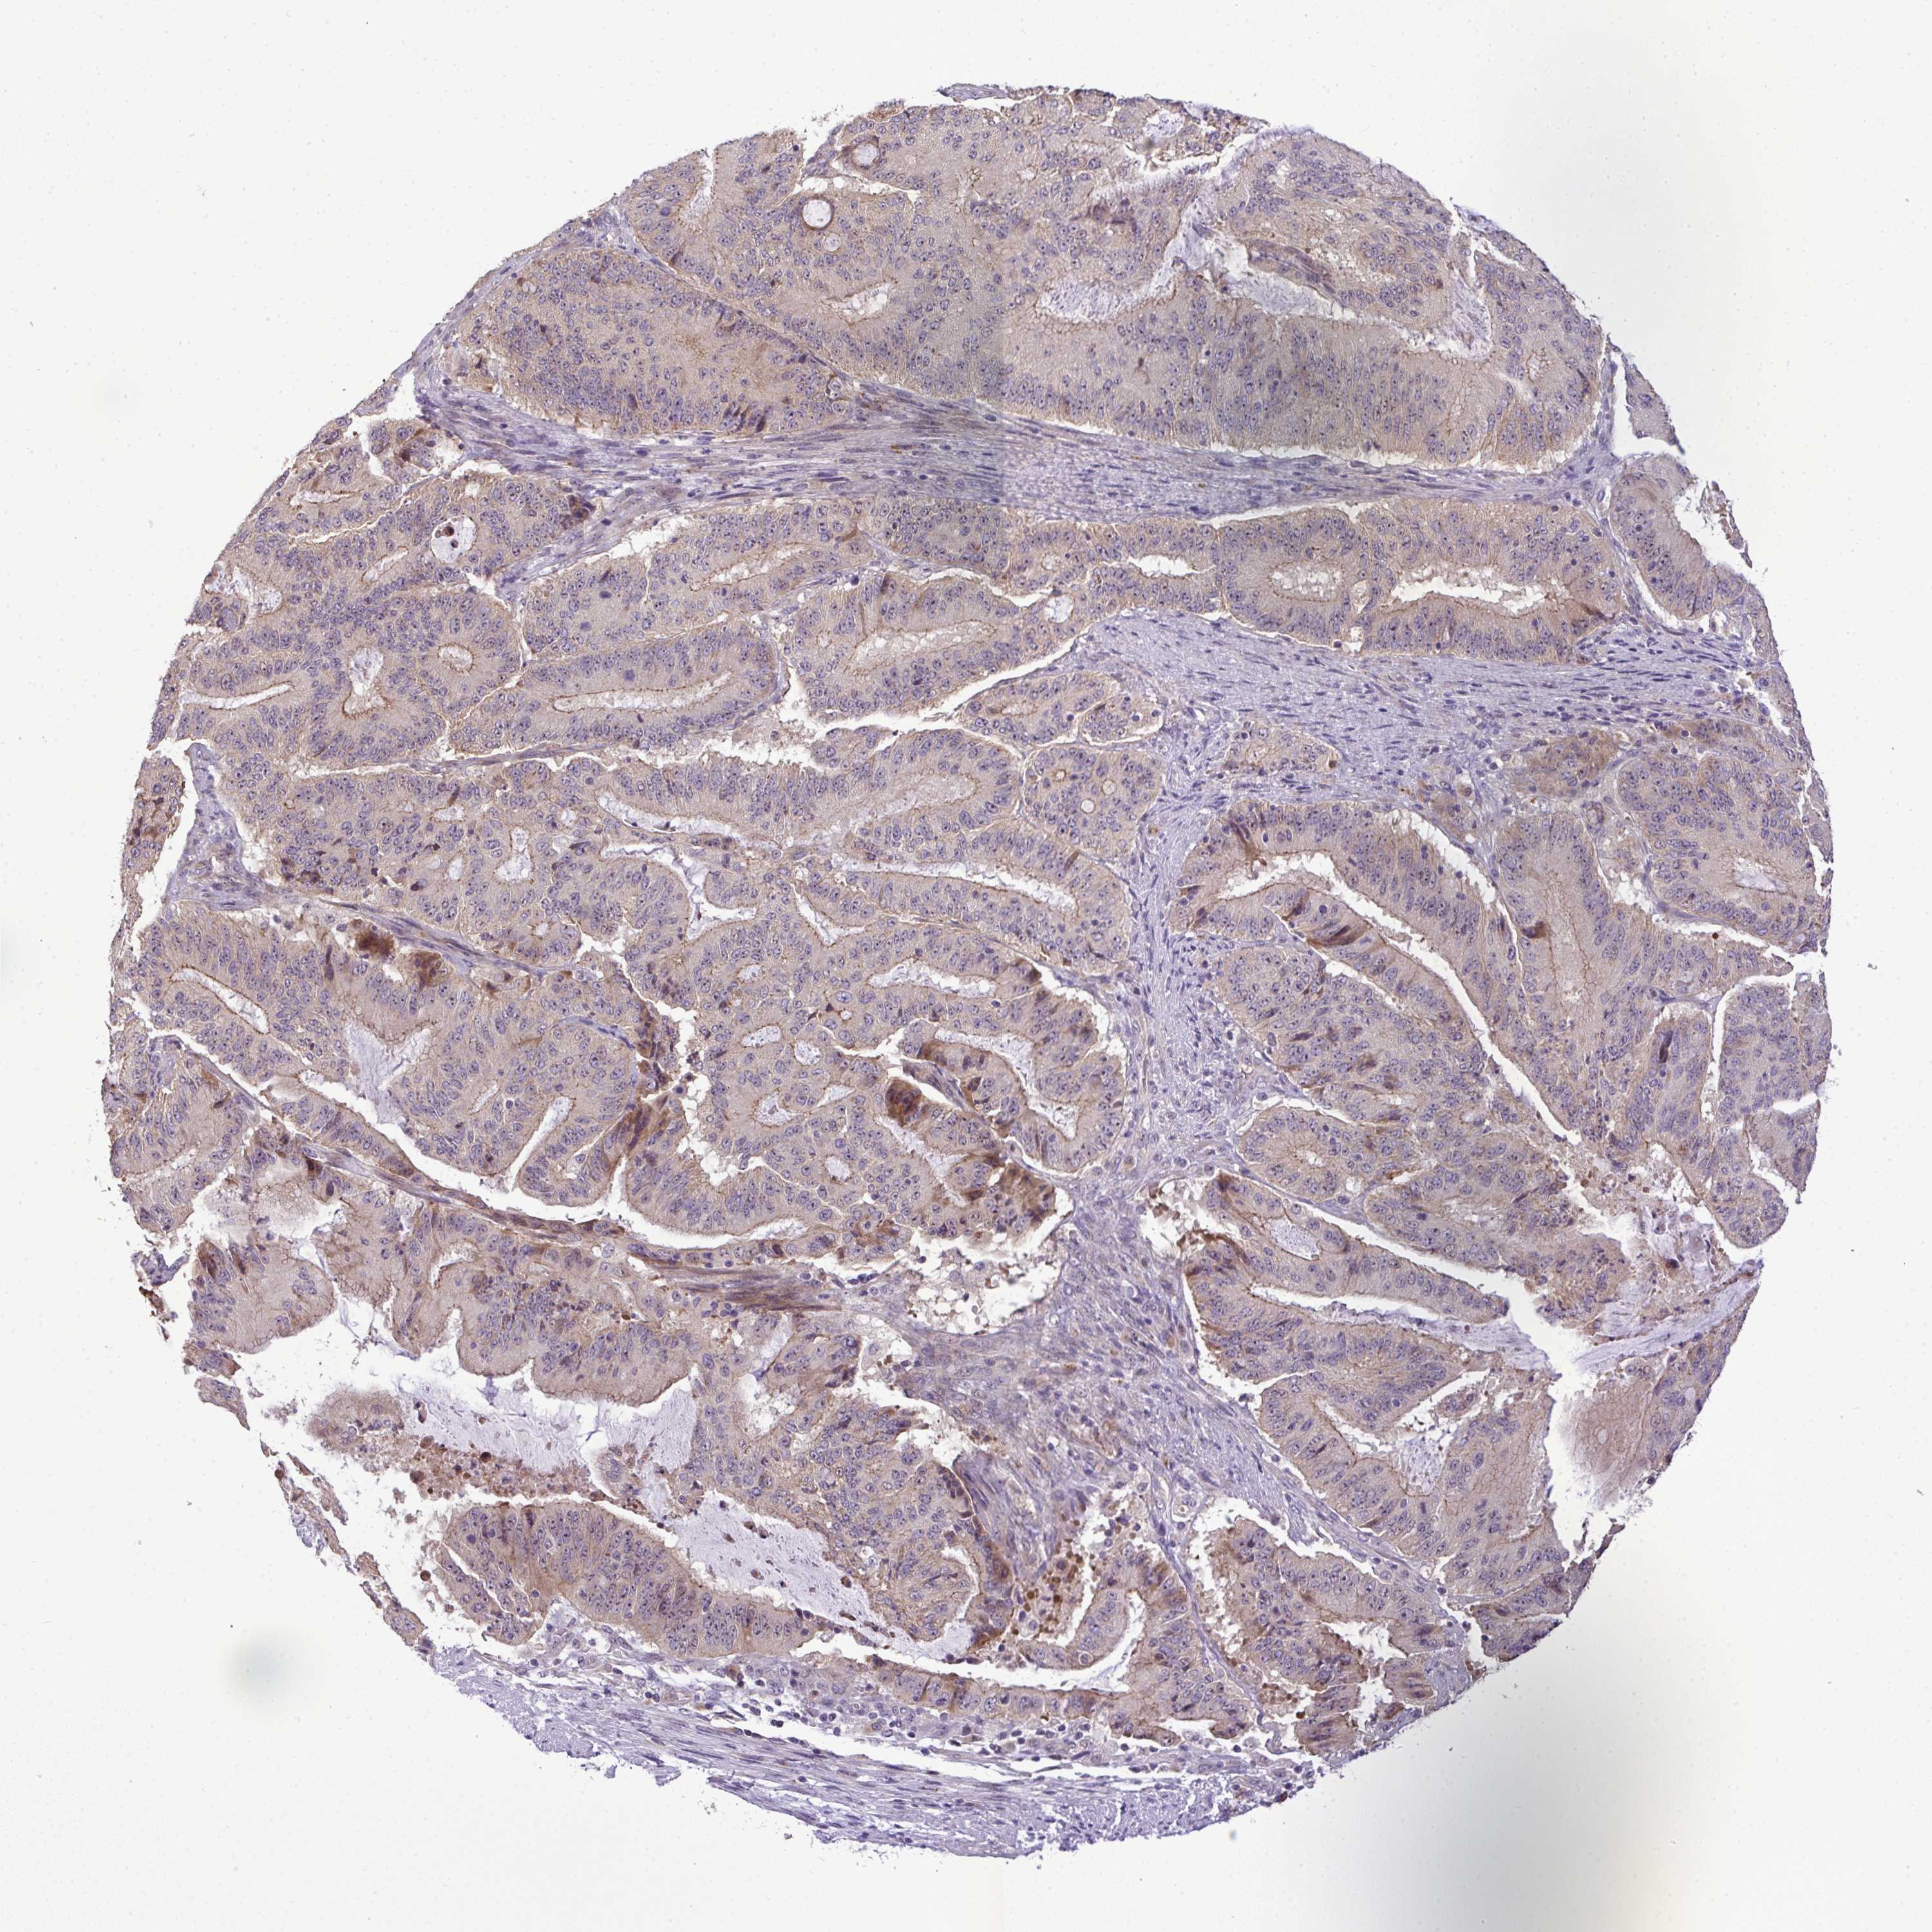

LIVER CANCER - Protein expressioni

A mouse-over function shows sample information and annotation data. Click on an image to view it in a full screen mode. Samples can be filtered based on level of antibody staining by selecting one or several of the following categories: high, medium, low and not detected. The assay and annotation is described here.

Note that samples used for immunohistochemistry by the Human Protein Atlas do not correspond to samples in the TCGA dataset.

Antibody stainingi

Antibody staining in the annotated cell types in the current human tissue is reported as not detected, low, medium, or high, based on conventional immunohistochemistry profiling in selected tissues. This score is based on the combination of the staining intensity and fraction of stained cells.

Each image is clickable and will lead to virtual microscopy that enables deeper exploration of all samples and also displays staining intensity scores, fraction scores and subcellular localization as well as patient and tissue information for each sample.

Antibody HPA050283

Antibody HPA054158

Staining

High

Medium

Low

Not detected

Intensity

Strong

Moderate

Weak

Negative

Quantity

>75%

75%-25%

<25%

None

Location

Nuclear

Cytoplasmic/membranous

Cytoplasmic/membranous,nuclear

Cholangiocarcinoma

Carcinoma, Hepatocellular, NOS